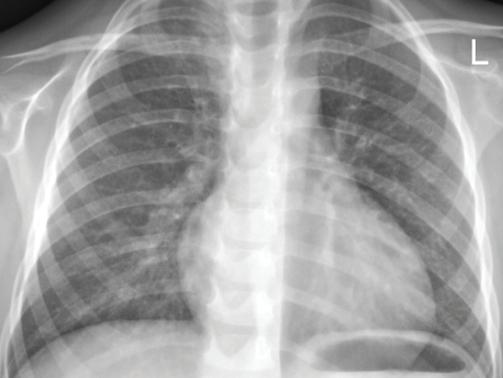

Придобитата в обществото пнев мония (ППО) все още остава чес та причина за заболяемост и смърт ност в световен мащаб. Честотата е най-висока при деца на възраст под 5 години и е от 10 до 40 случая на 1000 деца годишно[1,2]. Изчислено е, че ППО е причина за една пета от смъртните случаи при малки деца, с около два милиона смъртни случая годишно в развиващите се страни и развитият свят.

ност [СПИН] и тежка съпътстваща бе лодробна болест, като бронхиекта зии, кистична фиброза и хронична обструктивна белодробна болест [ХОББ])[8]. Известно е (главно на база та на проучвания на пунктати от бе лите дробове, проведени в развива щите се страни), че леката и умерена ППО се причинява главно от вируси, особено през първите години от жи вота, докато повечето случаи на теж ка ППО се причиняват от бактерии. Въпреки това е доказано, че грипни те вируси и респираторно-синцити алният вирус играят

в общността, където се на рича придобит в общността MRSA. Същият може да доведе до тежки бе лодробни инфекции, включително некротизираща и хеморагична пнев мония[7] Инфекцията с Pseudomonas aeruginosa е рядка при липса на спе цифични рискови фактори (скорош но антибиотично лечение, синдром на придобита имунна недостатъч

основна роля в причиняването на тежка и/или ус ложнена ППО. Значителен брой деца с ППО, причинени от атипични бак терии, показват сложно протичане, поради наличието на плеврален из лив[5] РИСКОВИ ФАКТОРИ И ЗАЩИТНИ МЕХАНИЗМИ НА ОРГАНИЗМА Микроорганизмите са разви ли разнообразни механизми, кои то благоприятстват колонизация та им в гостоприемника. Например, Парапневмонични усложнения – случаи от практиката Ю. Димитрова, Д. Хасанова, И. Цочева Отделение по педи атрия, УМБАЛСМ “Н. И. Пирогов” - София Придобитата в обществото пневмония все още остава честа причина за заболяемост и смърт ност в световен мащаб. Честотата е най-висока при деца под 5 години. S. pneumoniae и H. influenzae са водещите причинители на бактериална пневмония. При деца над 5-годиш на възраст зачестяват атипичните бактериални причинители - Mycoplasma pneumoniae и Chlamydophila pneumoniaе. Най-често тежките пневмонии, които протичат с усложнения, са вследствие на бактериални причинители и се изявяват с парапневмоничен излив, емпиема, мултилобарно заболяване, кавитарен абсцес, некротизираща пневмония, пневмоторакс, и бронхоплеврална фистула. ПЕДИАТРИЯ Ключови думи: Деца, ППО, парапневмонични усложнения.